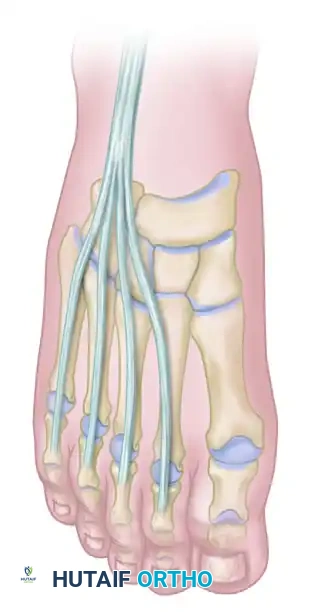

Anatomical representation of the plantar aponeurosis. The dense central and medial bands are the primary targets for release in the cavovarus foot.

Anatomy of the extensor digitorum longus (EDL) and extensor hallucis longus (EHL) tendons prior to transfer.

The Hibbs procedure involves the detachment of the extensor digitorum longus (EDL) tendons from the lesser toes. The proximal stumps of the EDL tendons are then tenodesed together and transferred into the middle cuneiform (or the base of the third metatarsal) via a bone tunnel or suture anchor.

Completed Hibbs and Jones procedures. The EHL is transferred to the first metatarsal, and the EDL tendons are transferred to the middle cuneiform, providing dynamic dorsiflexion to the midfoot.

This transfer serves a dual purpose: it eliminates the hyperextension force at the metatarsophalangeal (MTP) joints (allowing the toes to drop into a corrected position) and recruits the EDL to assist in global ankle and midfoot dorsiflexion.